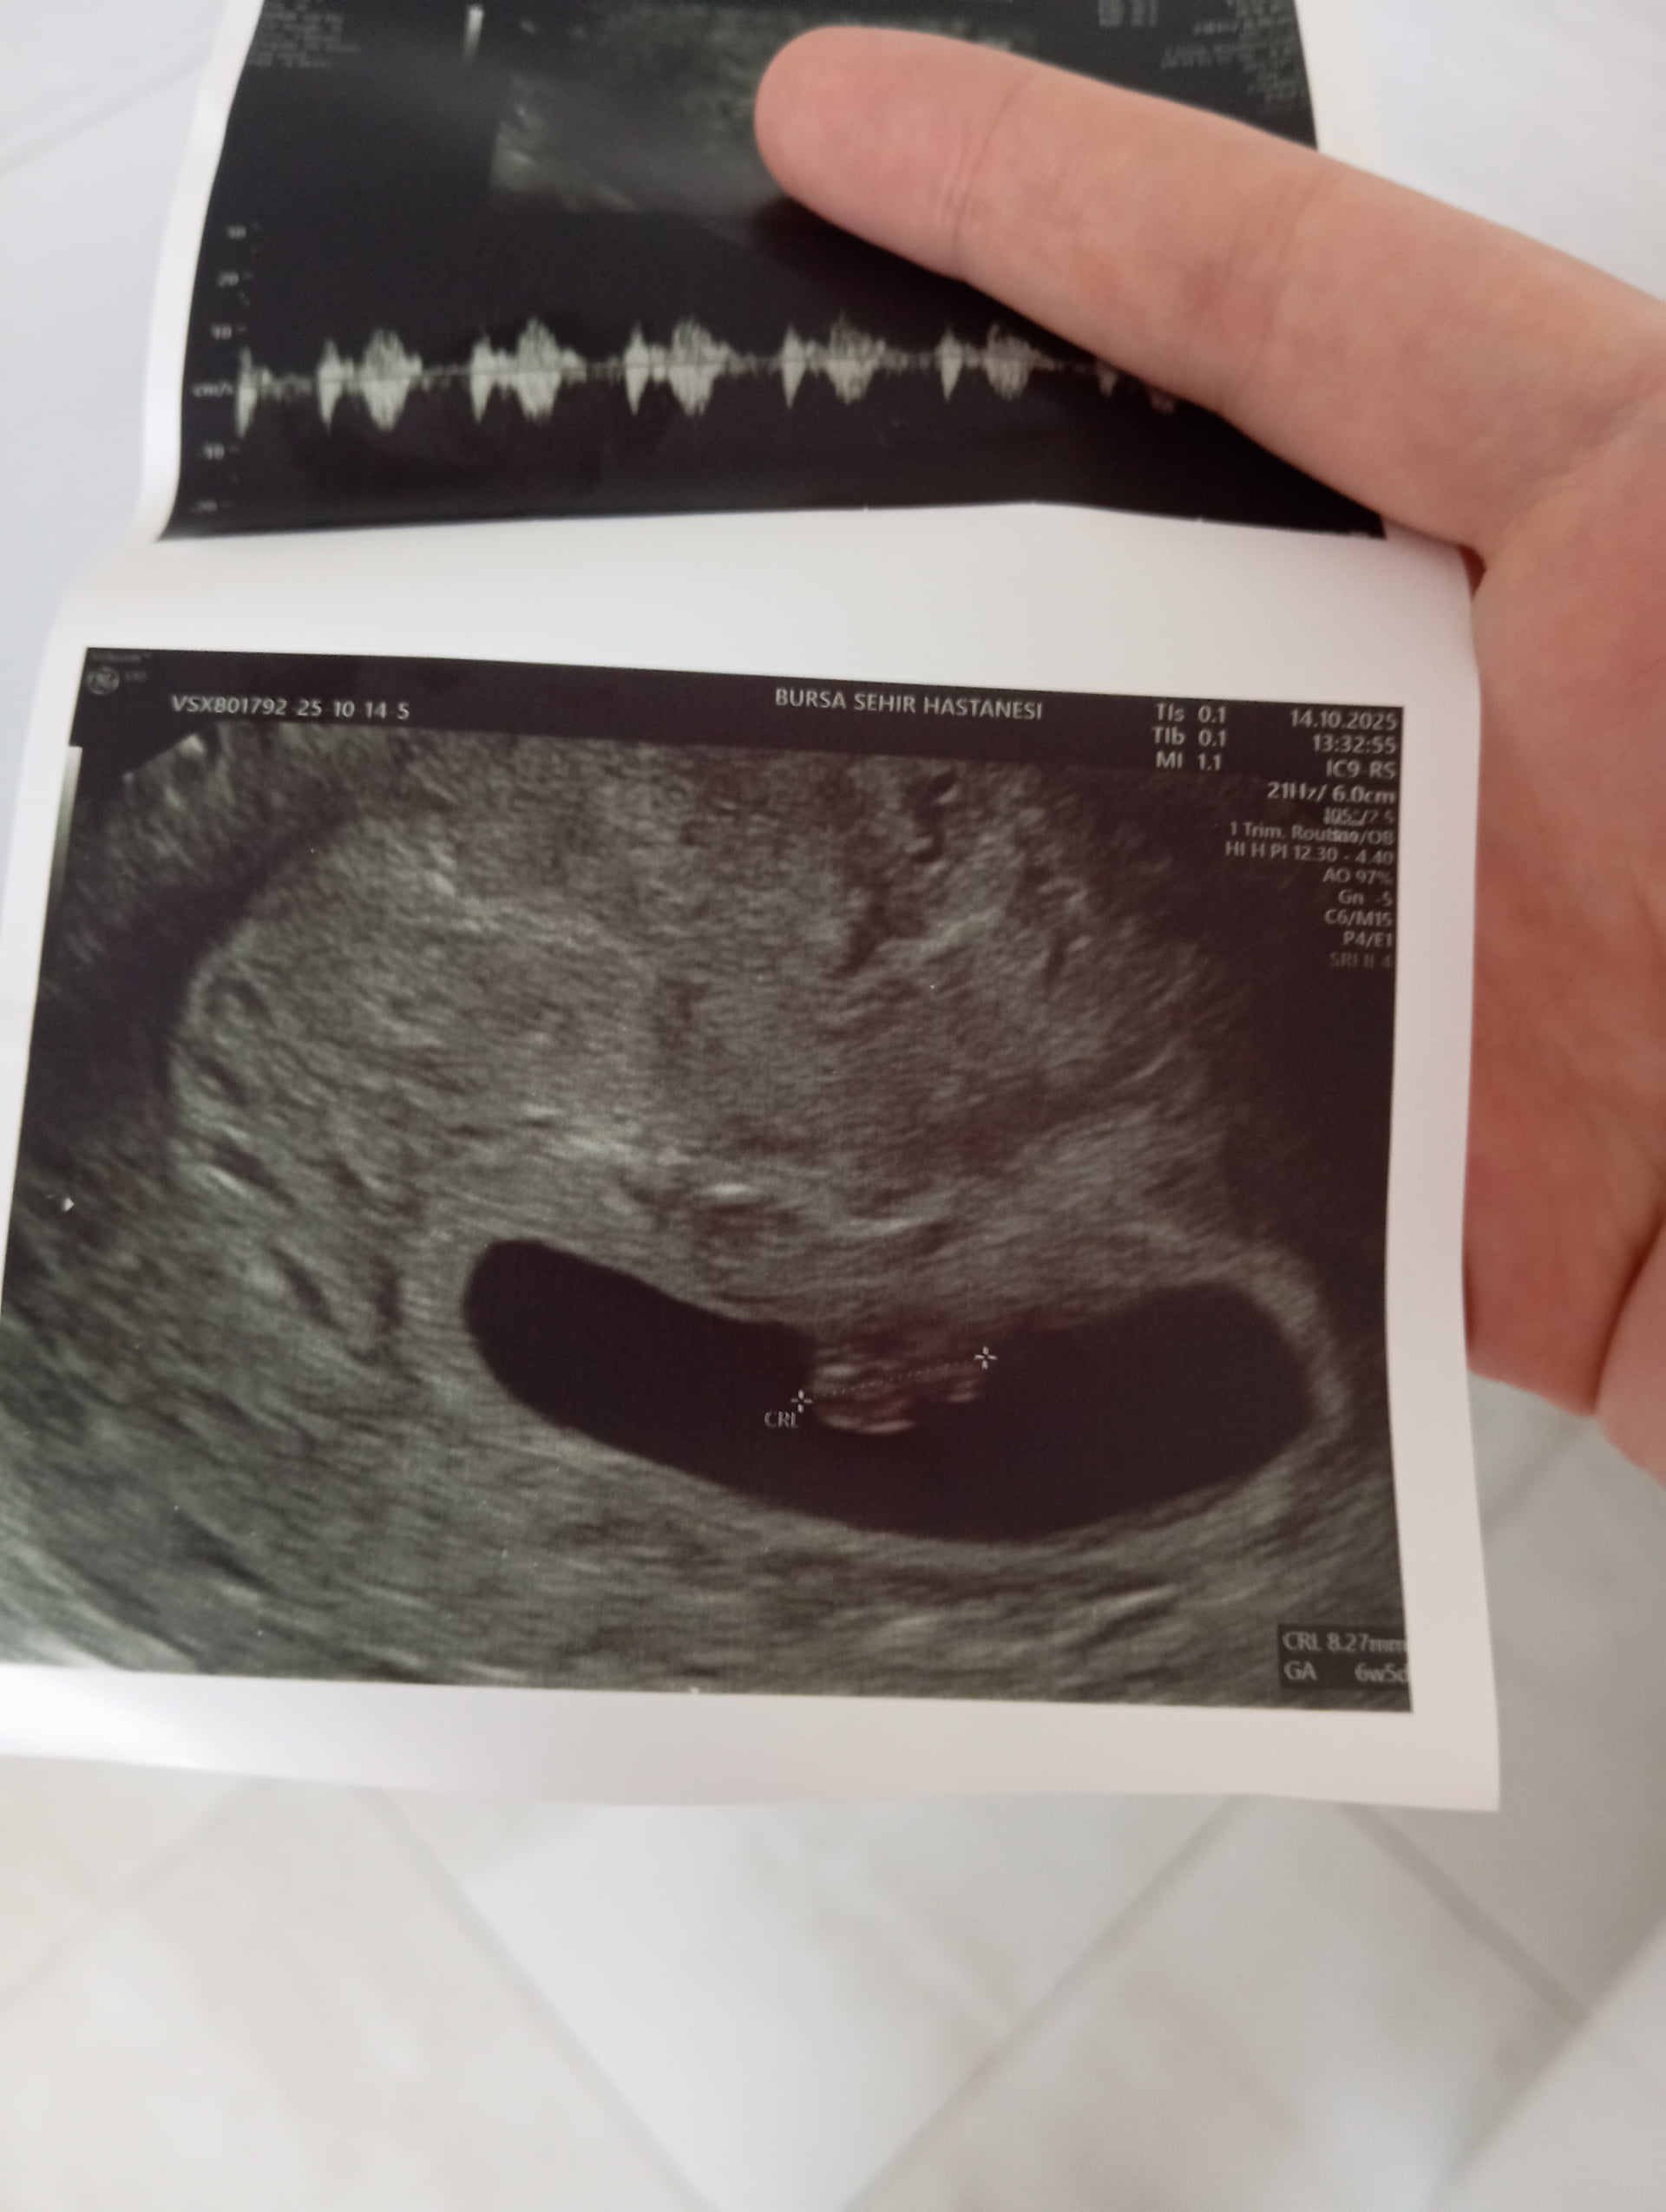

Anladgimdan değil ama erkek hissettim

bence erkek gibi

Erkek gibi

Erkek bebek kesesi gibi balım

Erkek gibii

galiba yuvarlak olanlar kiz yamuk yumuk sekilsizler erkek oluyo sizinki de erkek gibi

Büyük ihtimalle erkek canim

erkek gibi kesesi